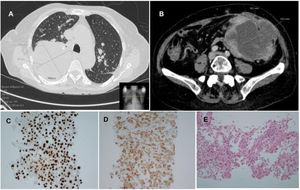

(A) Thoracic scan showing a pulmonary mass in the right upper lobe, measuring 90mm×87mm. (B) Abdominal and pelvic CT scan showing a mass on the left flank with 103mm×83mm. (C and D) The tumor cells express both TTF-1 and cytokeratin 7, which is compatible with pulmonary origin. (E) H&E staining: poorly differentiated adenocarcinoma.

An 82-year-old woman presented to the emergency department with a 15-day history of diarrhea (no blood or mucus), intermittent abdominal pain and asthenia. No fever associated and no history of cancer or smoking habits. Her medical history included hypertension, dyslipidemia, renal lithiasis and total hysterectomy. She had been followed up in stomatology in the previous month, for the recent appearance of an exophytic lesion in the lower right gingival. On emergency admission, physical examination revealed a palpable, bulky abdominal mass on the left flank and umbilical region. Blood tests revealed anemia (9.1g/dL), leukocytosis (20.55×109/L), neutrophilia (17.3×109/L) and high C reactive protein (27mg/dL). Thoracic and abdominal computed tomography scan showed two masses, one in the pulmonary right upper lobe, measuring 90mm×87mm, and the second on the left flank with 103mm×83mm (Fig. 1A and B). Abdominal, lung and gingival lesions histopathology revealed poorly differentiated pulmonary adenocarcinoma. Immunohistochemistry was negative for CDX2, cytokeratin20, GATA-3 and reactive for CK7 and TTF-1 (Fig. 1C–E). These findings support that the metastatic lesions were from a primary lung carcinoma. Unfortunately, the patient died two months after the diagnosis due to an infectious complication.